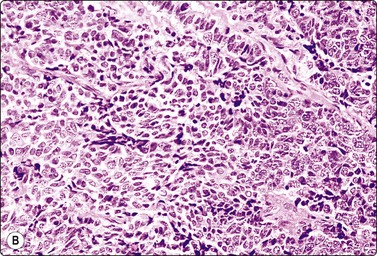

Tumors of more than one histologic type (mixed forms) (Figs 13.35 and 13.36)14,60,63,65

While the basic GCT types are infrequent in pure forms they are very frequent in mixed forms. Embryonal carcinoma and teratoma are each present in 47% of cases, and yolk sac tumors in 41%; 40% of TGCT contain varying numbers of syncytiotrophoblastic cells.12

image image

Fig. 13.36 Tumor of more than one histological type (mixed form)

(A) Well-differentiated glandular epithelium (right), large malignant cells similar to embryonal carcinoma (left) (MGG, HP); (B) Corresponding tissue section (A, H&E, IP; B, PAP, IP).

Criteria for diagnosis

Cellular aspirates; necrosis and hemorrhage frequent,

Three-dimensional clusters of epithelial malignant cells as described above

Coexisting teratomatous structures represented by mature or immature tissues originating from one or more blastodermal leaf: fusiform naked nuclei embedded in a myxoid background resembling embryonal mesenchyme; islets of cartilage; sheets of epithelial cells, which may be squamous, ciliated or intestinal (with goblet cells); bundles of fusiform cells with blunt ends reminiscent of leiomyoma; tight clusters of deeply stained bare nuclei may correspond to primitive neuroectodermal tissue.

The diagnosis of mixed forms is simple when malignant elements of an epithelial nature coexist with clear-cut teratomatous structures. Necrosis may obscure the neoplastic cells and the teratomatous component may be only minor or even absent. This can be explained by its greater cohesion causing under-representation in FNA samples. As a result, the differential diagnosis between mixed TGCT and embryonal carcinoma is sometimes difficult or impossible.14,59-61,65,66 The presence of multinucleated syncytial cells is not diagnostic of choriocarcinoma.